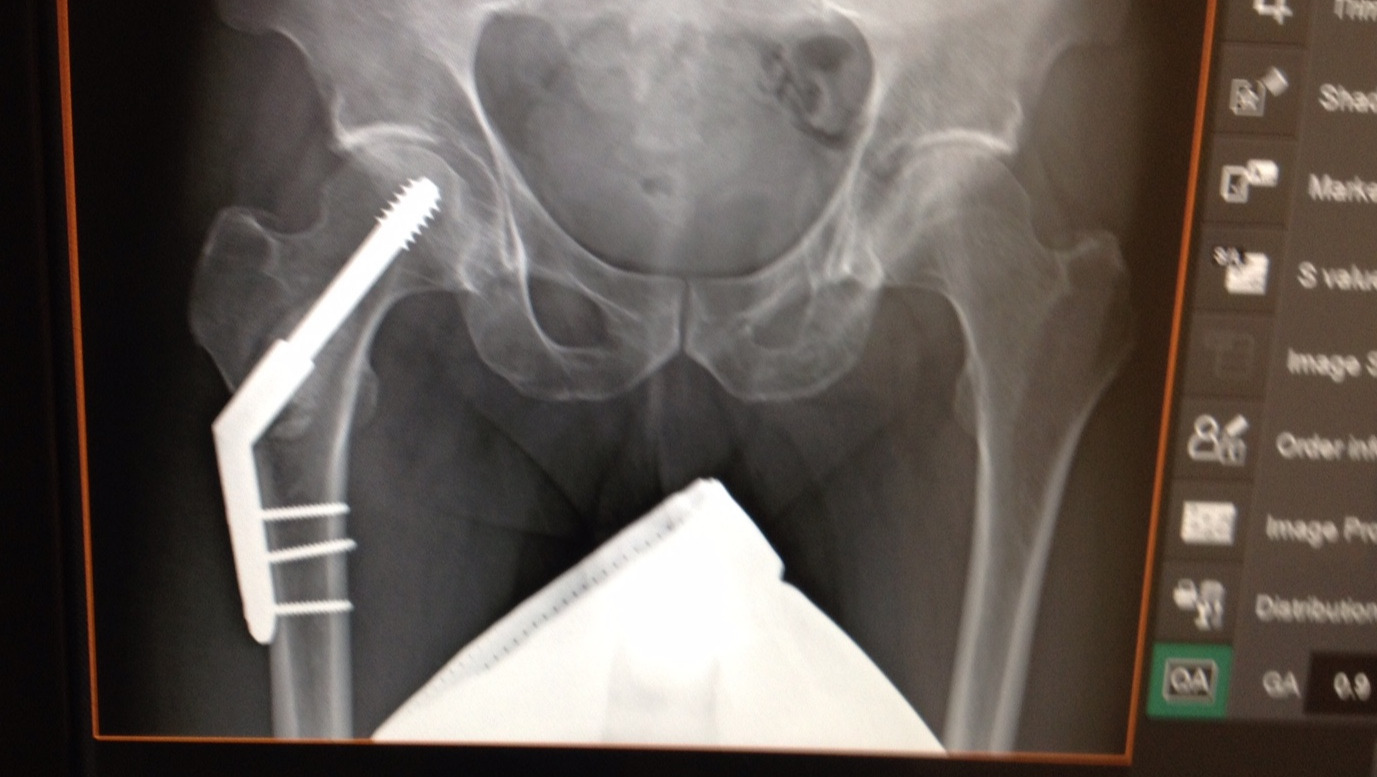

Jeff has fought and persevered, and over 5 years later he is still fighting an uphill battle of chemo, radiation, surgeries, and personal life struggles, but he is surviving and even more when he can.

There have been good days and bad. The cancer and treatments have devastated him both physically, emotionally and mentally… unfortunately there have been more bad than good. (The pictures above and below show both)

The cancer has eaten at his bones requiring hip surgeries, and more than once reduced him to less than 115lbs.